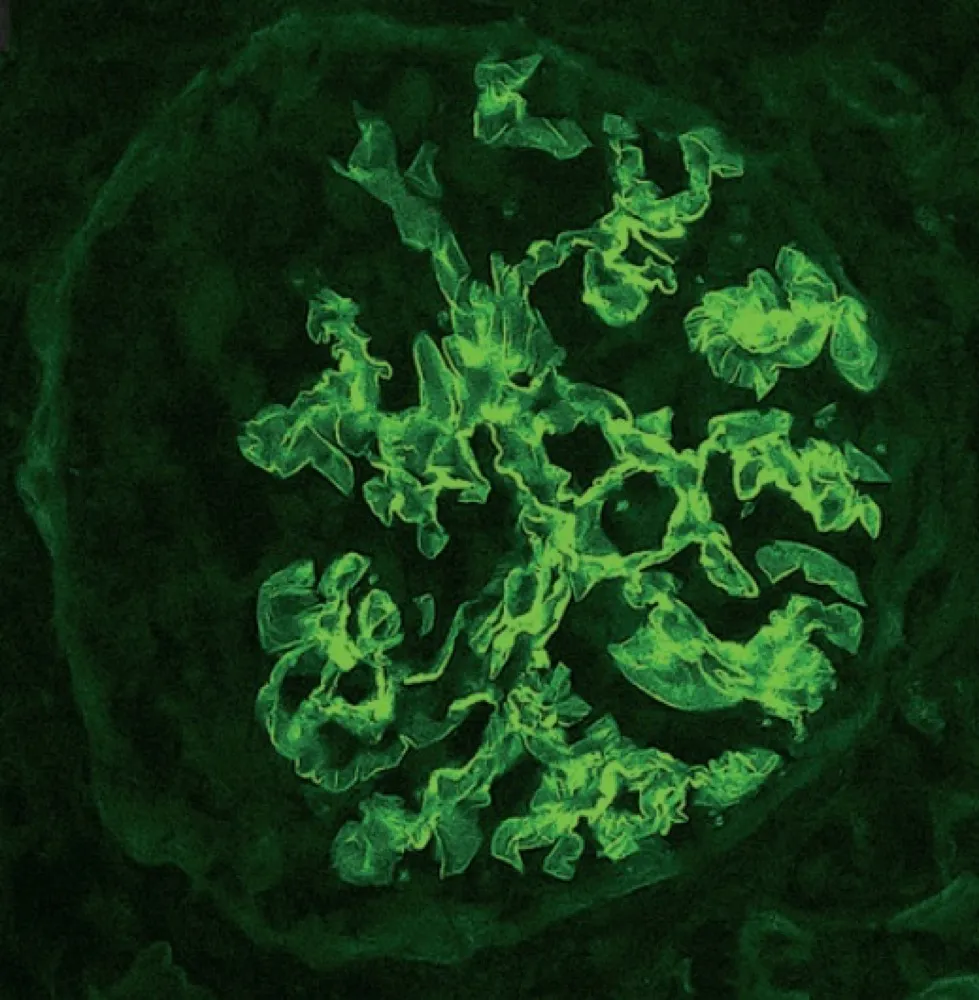

Uma causa incomum de hematúria glomerular intermitente!

Uma causa incomum de hematúria glomerular intermitente!

Hematúria pós infecção, caso clínicos para auxiliar no entendimento de causas glomerulares comuns e raras...